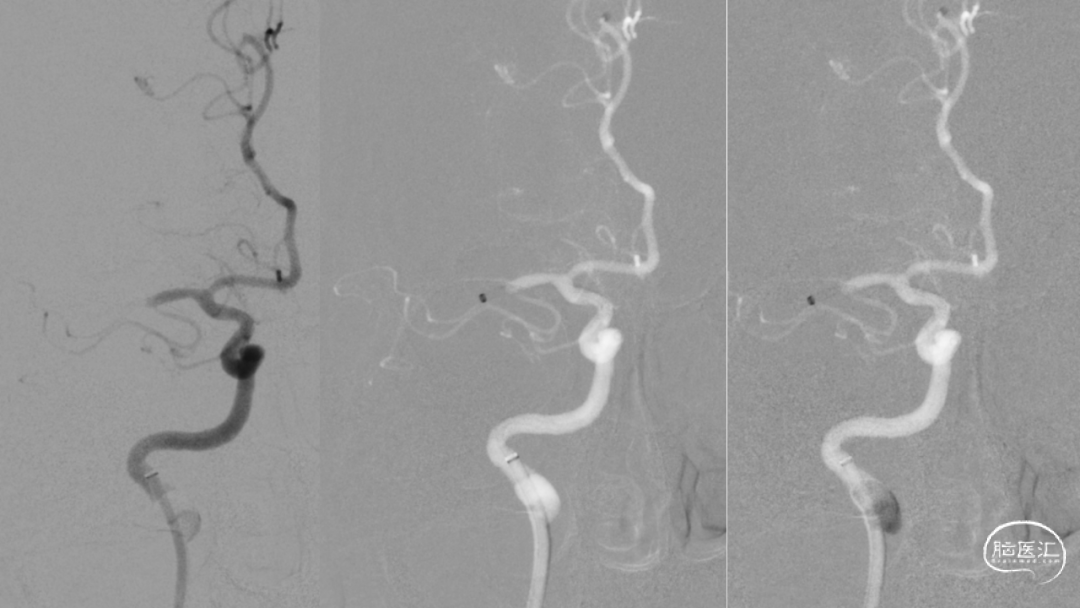

取之有道·第54期|李子付:Flowgate2取栓应用

看李子付解“取之有道”

滑动浏览更多内容